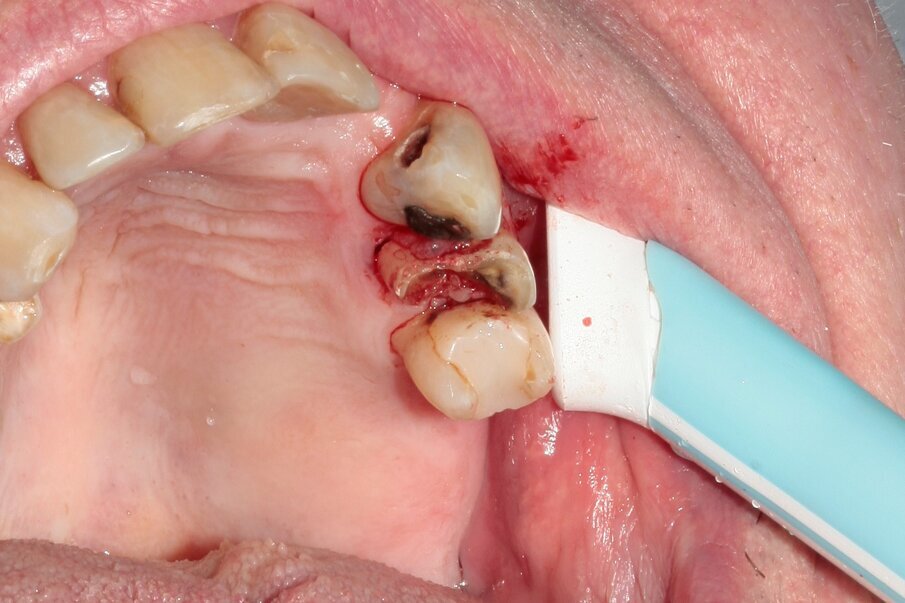

A 70-year-old female patient visited our clinic owing to a fractured maxillary first molar. Tooth #24 had previously had a large composite restoration that was no longer in place at the time of the dental appointment.

Tooth #24 was severely decayed down to the marginal bone edge.

Figs. 2–4: The tooth was luxated with Luxator P4 (dual edge, lilac).